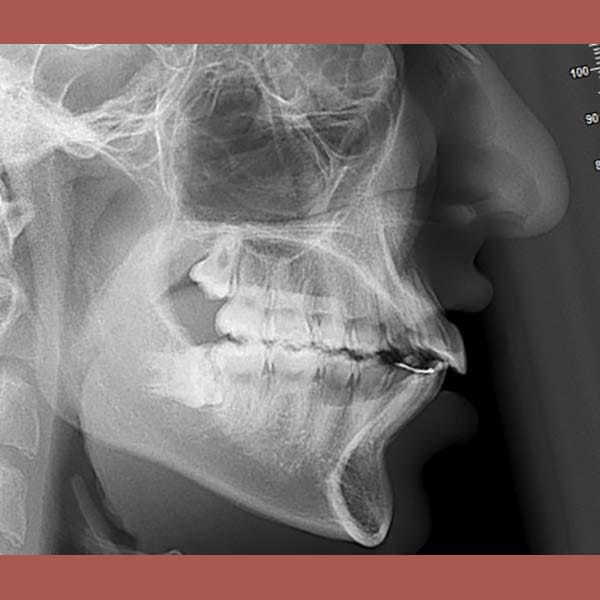

عندما يكون بروز الأسنان ناتجاً عن تراجع الفك السفلي، يمكن للتدخل المبكر أن يحل المشكلة من جذورها. بصفتي أخصائي تقويم أسنان في العين، أستخدم الأجهزة الوظيفية لتصحيح علاقة الفكين. هذه الحالة توضح كيفية علاج بروز الأسنان بدون خلع باستخدام جهاز وظيفي ثابت.

وضع الدكتور خالد الكاتب خطة علاجية متكاملة بدون قلع أي أسنان. تم استخدام مزيج من: